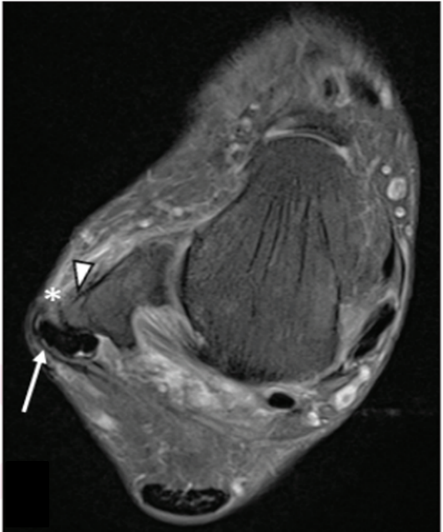

腓骨肌腱脱位 (长箭头),腓骨骨膜炎 (三角箭头),腓骨支持带损伤 (*)。图源:DOI:10.2214/AJR.20.23964